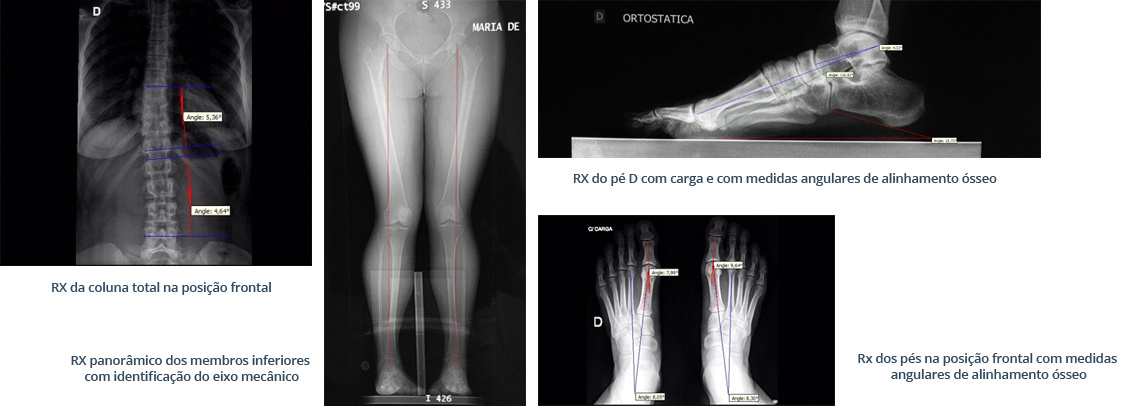

Em conjunto, realizamos uma análise biomecânica estática da coluna e dos membros inferiores. Dessa forma, identificamos o eixo mecânico e quantificamos deformidades ósseas, informações valiosas que orientam tratamentos clínicos ou cirúrgicos. Aliás, essa avaliação possibilita um acompanhamento preciso da posição biomecânico de cada paciente. Por fim, a Avaliação Biomecânica e Postural dos Pés permite analisar como você pisa, distribui o peso e como seus pés se comportam durante a marcha e em repouso. Além disso, utilizamos equipamentos específicos para identificar pontos de pressão excessiva, desalinhamentos e disfunções que podem levar a dores, calosidades, fascite plantar, tendinites e até mesmo joanetes. Essa análise aprofundada ajuda a determinar se você possui pé plano, pé cavo, ou outras alterações que impactam sua postura e movimento. Portanto, é um passo crucial para um diagnóstico preciso e um plano de tratamento eficaz.